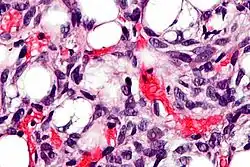

Liposarcoma

Los lipoblastos pueden verse en los liposarcomas[5] y característicamente tienen un citoplasma abundante, claro y multivacuolado y un núcleo mellado y con tinción oscura (hipercromático).